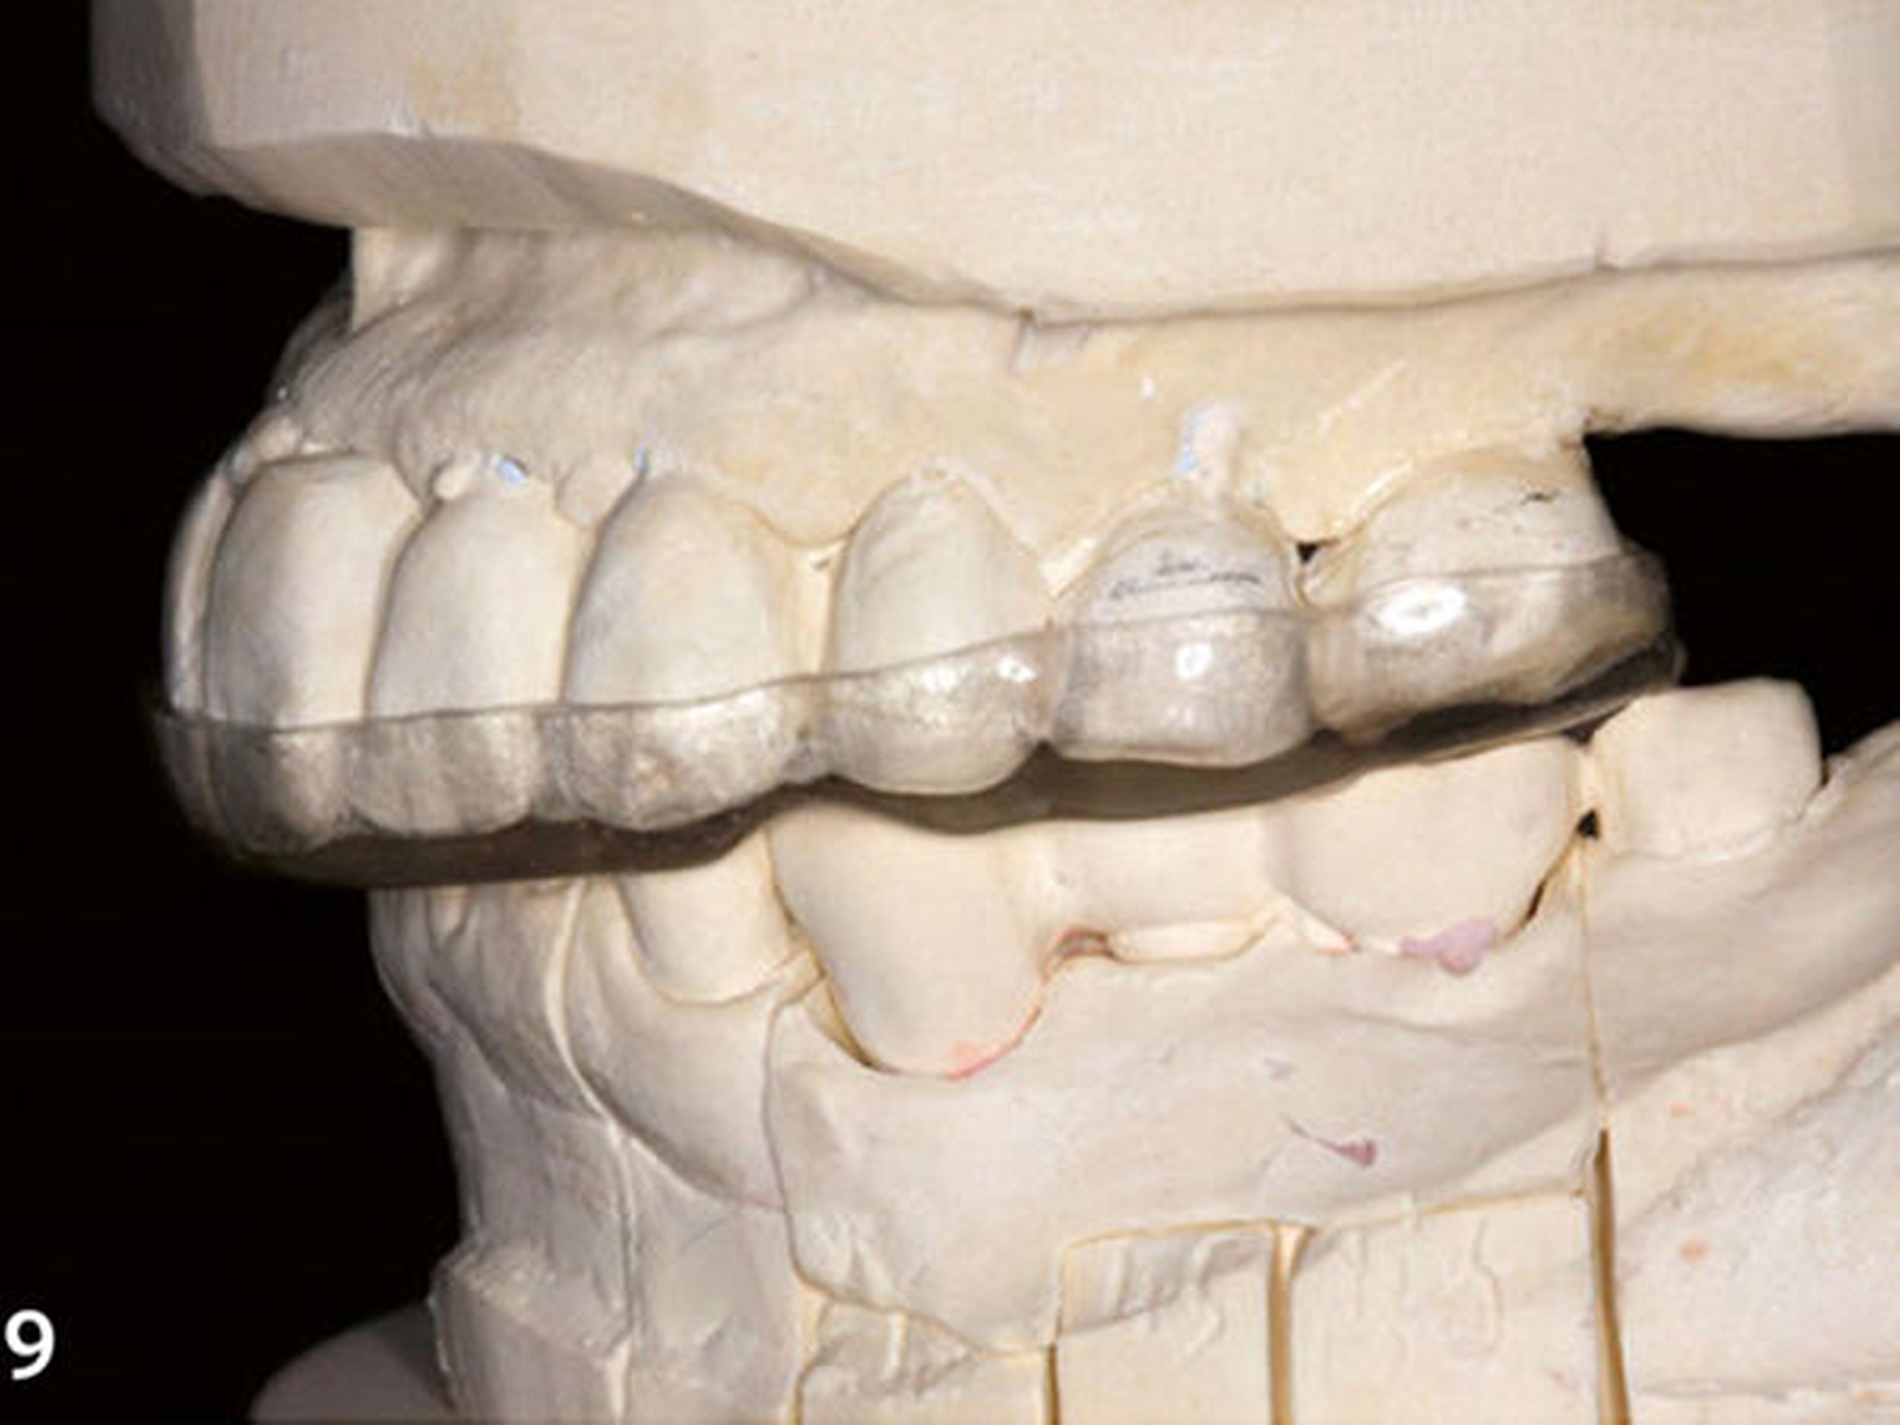

Im Labor wurde das Unterkiefermodell mithilfe des Registrats neu in der zentrischen Kondylenposition im Artikulator montiert und dabei dessen Stützstift gleichzeitig auf die angestrebte therapeutische vertikale Kieferrelation eingestellt. Anschließend wurde in dieser neuen Modellsituation eine stabilisierende Okklusionsschiene (harte Schiene mit adjustierter Oberfläche) angefertigt, um die Änderung der horizontalen und vertikalen Kieferposition reversibel an der Patientin simulieren zu können (Abb.9) (Ahlers et al. 2016).

Dritte Laborphase: Nach der komplikationsfreien Evaluation der therapeutischen horizontalen und vertikalen Bisslage an der Patientin wurde das Unterkiefermodell im zahntechnischen Labor mithilfe der Okklusionsschiene neu einartikuliert (Abb.11). Es wurde anschließend ein segmentweises Wax-up der idealen Okklusion erstellt (Bartlett 2016; Muts et al. 2014). Im ersten Schritt des Wax-up erfolgte die Rekonstruktion der okklusalen Anteile der Seitenzähne bis auf die endständigen Zähne beiderseits (Abb.12). Dadurch kann die nachfolgend angefertigte erste Übertragungsschiene später im Mund an den letzten Zähnen der Zahnreihe und im Frontzahnbereich definiert abgestützt werden (Schmidlin et al. 2009c). Der teilaufgewachste Unterkiefer wurde mit feinzeichnendem Silikon dupliert und auf diesem Gipsmodell eine Hilfsschiene in der Tiefziehtechnik (Schiene1) für die intraorale Übertragung des Wax-up mit Komposit angefertigt (Abb.13). Diese als Formträger verwendete Schiene wird aus einer Polyethylenfolie (Copyplast, Scheu Dental) tiefgezogen, die sich nicht mit Acrylaten verbindet, um sich von den damit eingebrachten Kompositaufbauten intraoral problemlos wieder abnehmen zu lassen.